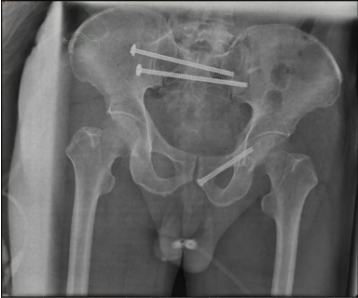

术中,岳晓东主任依托HoloSight平台规划的置钉路线,精准的为患者进行骶髂关节螺钉固定。

术后影像

经过术中、术后影像学检查确认,骨折复位良好,内固定位置满意。手术仅留下几个1-2厘米左右的小切口,术中出血约100ml,术后48小时患者即可在床上自主活动,现恢复良好。